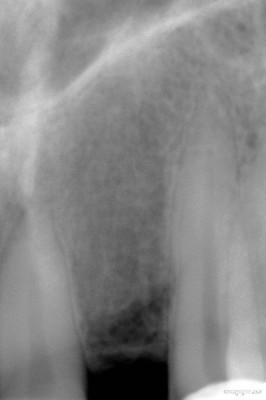

Radiografía final